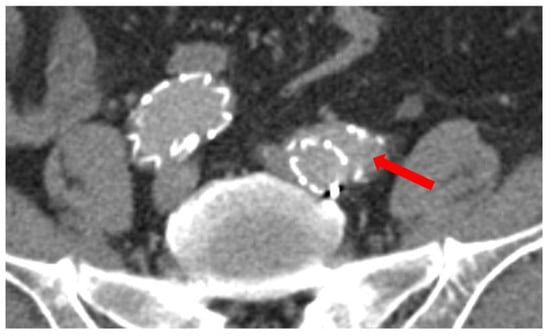

3.2.3. Iliac Landing Zone

3.5. Iliac Limb Detachment

Preoperative and Perioperative Factors